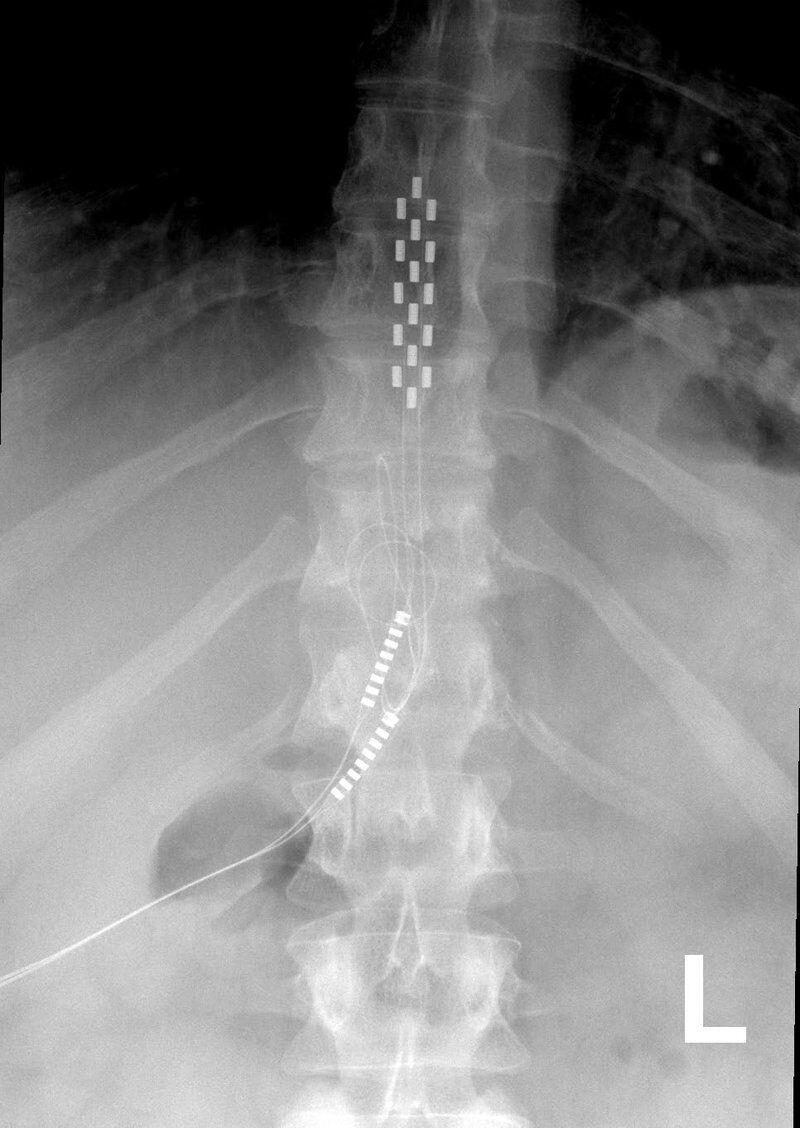

During the implant, a local anesthetic is injected to numb the low back. Using X-ray fluoroscopy, a hollow needle is inserted subcutaneously into the epidural space between the bone and spinal cord. The doctor will insert a single trial lead and position it within a specific region near the spinal cord. The wires will connect to an external generator worn on a belt.

The patient will be sent home and instructed to monitor and care for the incision. Doctors will request the patient to keep a written log of the stimulation settings during different activities and note the level of pain relief. After a trial period spanning between 4 to 7 days, the patient will return to the medical center to finalize with the attending doctor if a permanent form of SCS will be needed. If the trial is successful, a second surgery will be scheduled, which by then will involve a full set of SCS leads that will cover the entire pain area identified for treatment. The surgery typically takes about an hour..